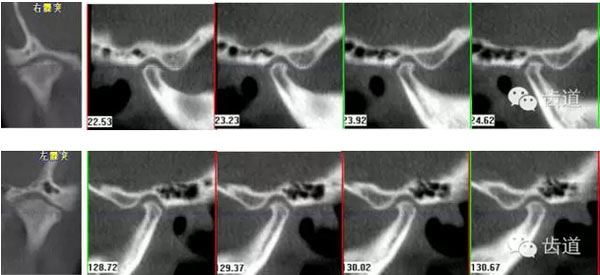

下頜后縮為主要特征的骨性II類,高角,前牙開(kāi)合,上前牙略唇傾,雙側(cè)下頜升支及髁狀突不對(duì)稱,右側(cè)較左側(cè)粗壯,左側(cè)髁狀突外斜面曾有吸收,但現(xiàn)骨白線與皮質(zhì)骨已比較連續(xù),上呼吸道正常。上

治療后關(guān)節(jié)截圖(CBCT)